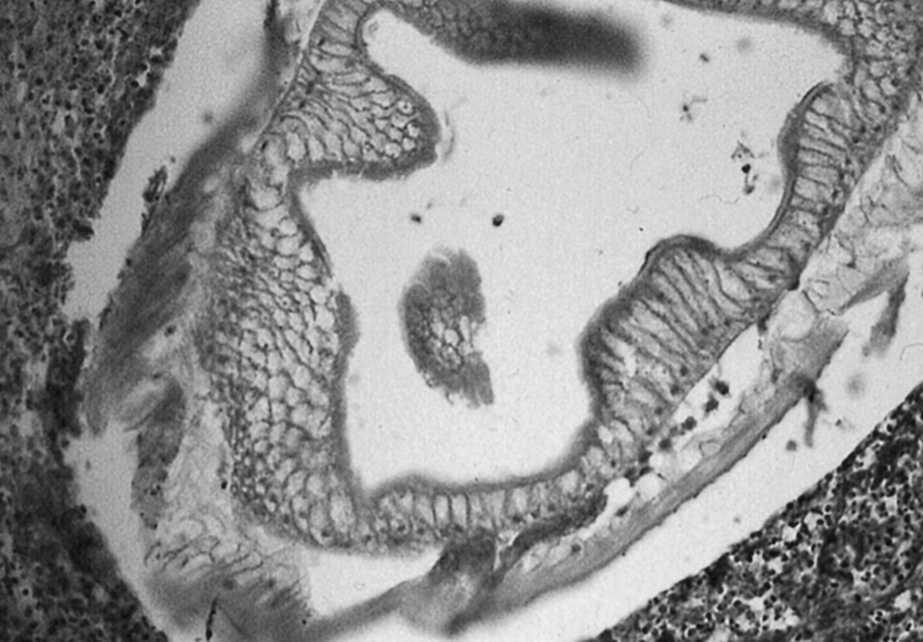

Varón de 63 años que presenta dolor abdominal difuso e intenso, asociado a náuseas, vómitos y fiebre. El paciente manifestó que había ingerido boquerones (Engraulis encrasicholus) en vinagre 3 días antes. En la exploración destacaba un abdomen distendido, timpanizado con peritonismo generalizado. La analítica revelaba leucocitosis con neutrofilia y en la tomografía computarizada (TC) abdominal se apreciaba un segmento de íleon distal de unos 15 cm muy engrosado, con asas intestinales proximales muy dilatadas, abundante líquido intraperitoneal y engrosamiento del antropíloro. En la intervención quirúrgica se objetivó una zona de ileítis perforada con un exudado fibrinopurulento sobre una serosa muy congestiva. Se resecó el segmento afectado, cuyo examen macroscópico reveló la presencia de un parásito (fig. 1; punta de aguja) en una zona fisurada de la mucosa. Existía, además, un importante edema transmural con múltiples erosiones y petequias en la mucosa. El examen histopatológico confirmó la presencia transmural de un parásito tipo Anisakis sp., así como un importante edema e infiltración periparasitaria y transmural de neutrófilos, eosinófilos, linfocitos y células plasmáticas (fig. 2).

Figura 1.